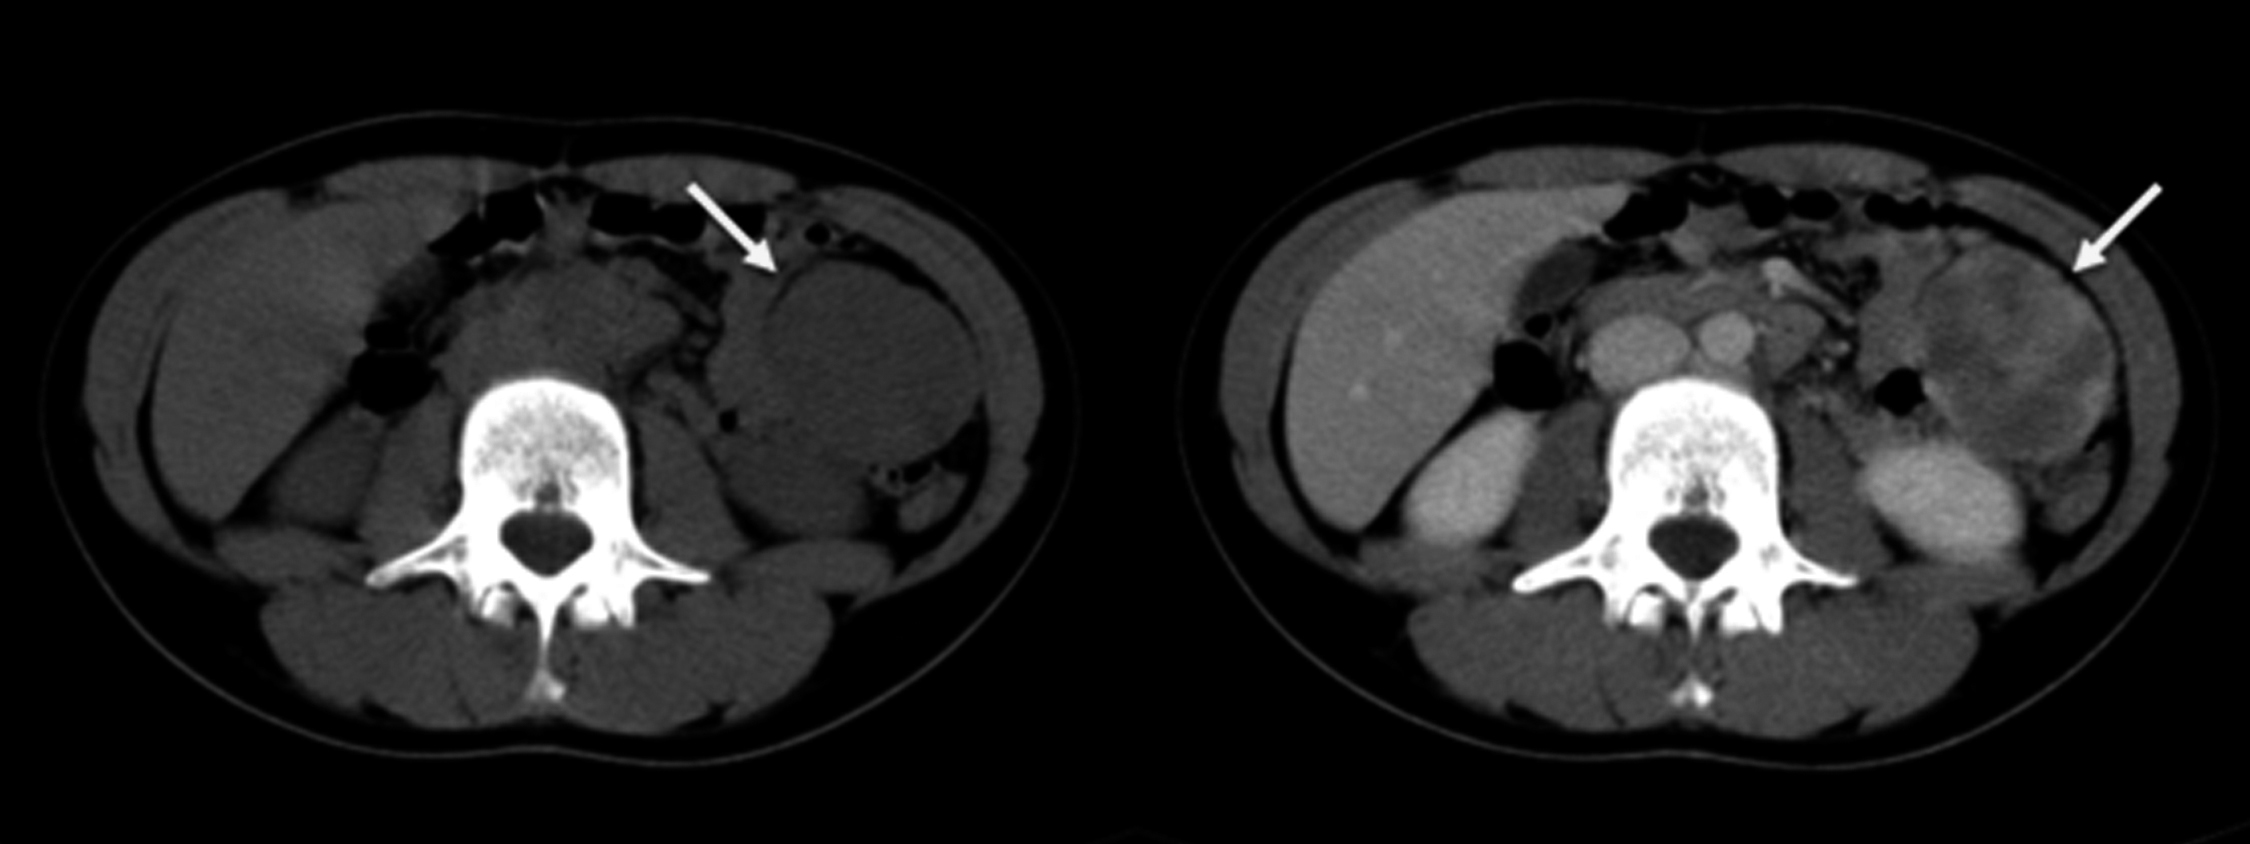

Se realiza TC de abdomen y pelvis sin y con medio de contraste intravenoso. Se identifica a nivel de flanco izquierdo masa sólida, bilobulada, de bordes lisos, bien definida, que mide 80 x 50 x 50 mm de diámetro en sus ejes L, T, AP respectivamente, con realce heterogéneo con el medio de contraste. Se encuentra por delante del colon descendente y por fuera de las asas delgadas e impresiona tener plano de separación con dichas estructuras, por lo que se interpreta que probablemente corresponda a una masa intraperitoneal (Figura 6).

Figura 6

TC de abdomen: corte axial previo al contraste donde se evidencia a nivel del flanco izquierdo masa sólida bilobulada con bordes lisos (a), que muestra realce heterogéneo luego de la administración de contraste (b) (flechas)

Se realiza otra TC de abdomen y pelvis, sin y con medio de contraste intravenoso. Se identifica masa sólida de similares características que en la TC previa, pero actualmente localizada en hipocondrio izquierdo, subhepática, adyacente a la curvatura gástrica mayor y asas delgadas. Se observan asas delgadas distendidas con niveles hidroaéreos, con zona de transición a nivel pelviano. Se plantea oclusión por bridas. (Figura 7)

Figura 7

TC de abdomen: reconstrucción en plano coronal (a) y corte axial (b), donde se observa, seis meses después de la primera TC, la misma masa sólida pero actualmente ubicada en el hipocondrio izquierdo (flechas) que asocia dilatación de asas delgadas.